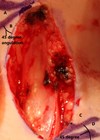

How I Do It - Auricular reconstruction: Helical advancement flap

As the incidence of cutaneous malignancy increases further due to both the ageing population and greater disease awareness, the demand for surgical resection within the high-risk regions of the face, including the pinna, is rising [1,2]. Approximately 50% of all...